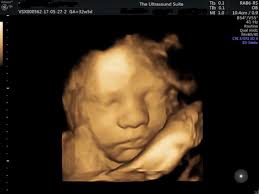

Are 3d Ultrasounds Worth The Extra Money Mom Com

Are 3d Ultrasounds Worth The Extra Money Mom Com from images.ctfassets.net